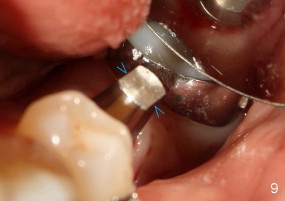

The tooth #19 has been lost for 8 years with tilting of #18 (black line in Fig.1). A 6x8 mm Bicon implant (3 mm post) was placed as distal as possible (I in Fig.2). Three months later, the implant was uncovered with evidence of osteointegration (arrowheads in Fig.3). A 4x6.5 mm 0 degree non-shouldered abutment with 3 mm post (A) was inserted into the implant well. The flat surface of the abutment needed to face distal in order to seat the abutment without interference. The implant/abutment complex was used as an anchorage to upright #18. The tooth #17 was extracted prior to orthodontic treatment (compare Fig.5,6 vs. 1-3). A bracket was bonded to Jet temporary crown of #19 and open coil spring was placed between #18 and 19. In the first two months, distalization of #18 is limited (between black and white lines in Fig.4), partially due to the fact that the bracket of #19 was debonded quite easily. A premolar band (B in Fig.5) was cemented to the temporary crown of #19. In another two months, the tooth #18 was pushed to desired position (arrowhead) under the tension of open coil spring (*). The mesial crest height of #18 was increased during uprighting (arrow, as compared to Fig.1-3). A new temporary crown was fabricated to fit the enlarged space of #19 with cementation of a molar band. The next problem is that the new molar temporary crown was easily dislodged from the 4x6.5 mm abutment even with a permanent cement. A larger abutment (5x6.5 mm) was used (Fig.6), with relining the temporary crown. The upper end of the larger abutment has sharp edge (Fig.8: white arrowhead, as compared to rounded edge of the smaller abutment (Fig.7). This may also contribute to better retention. In another 3 months, the temporary crown was dislodged again. An even larger abutment (6.5x6.5 mm with two flat surfaces (blue arrowheads in Fig.9) was adopted.